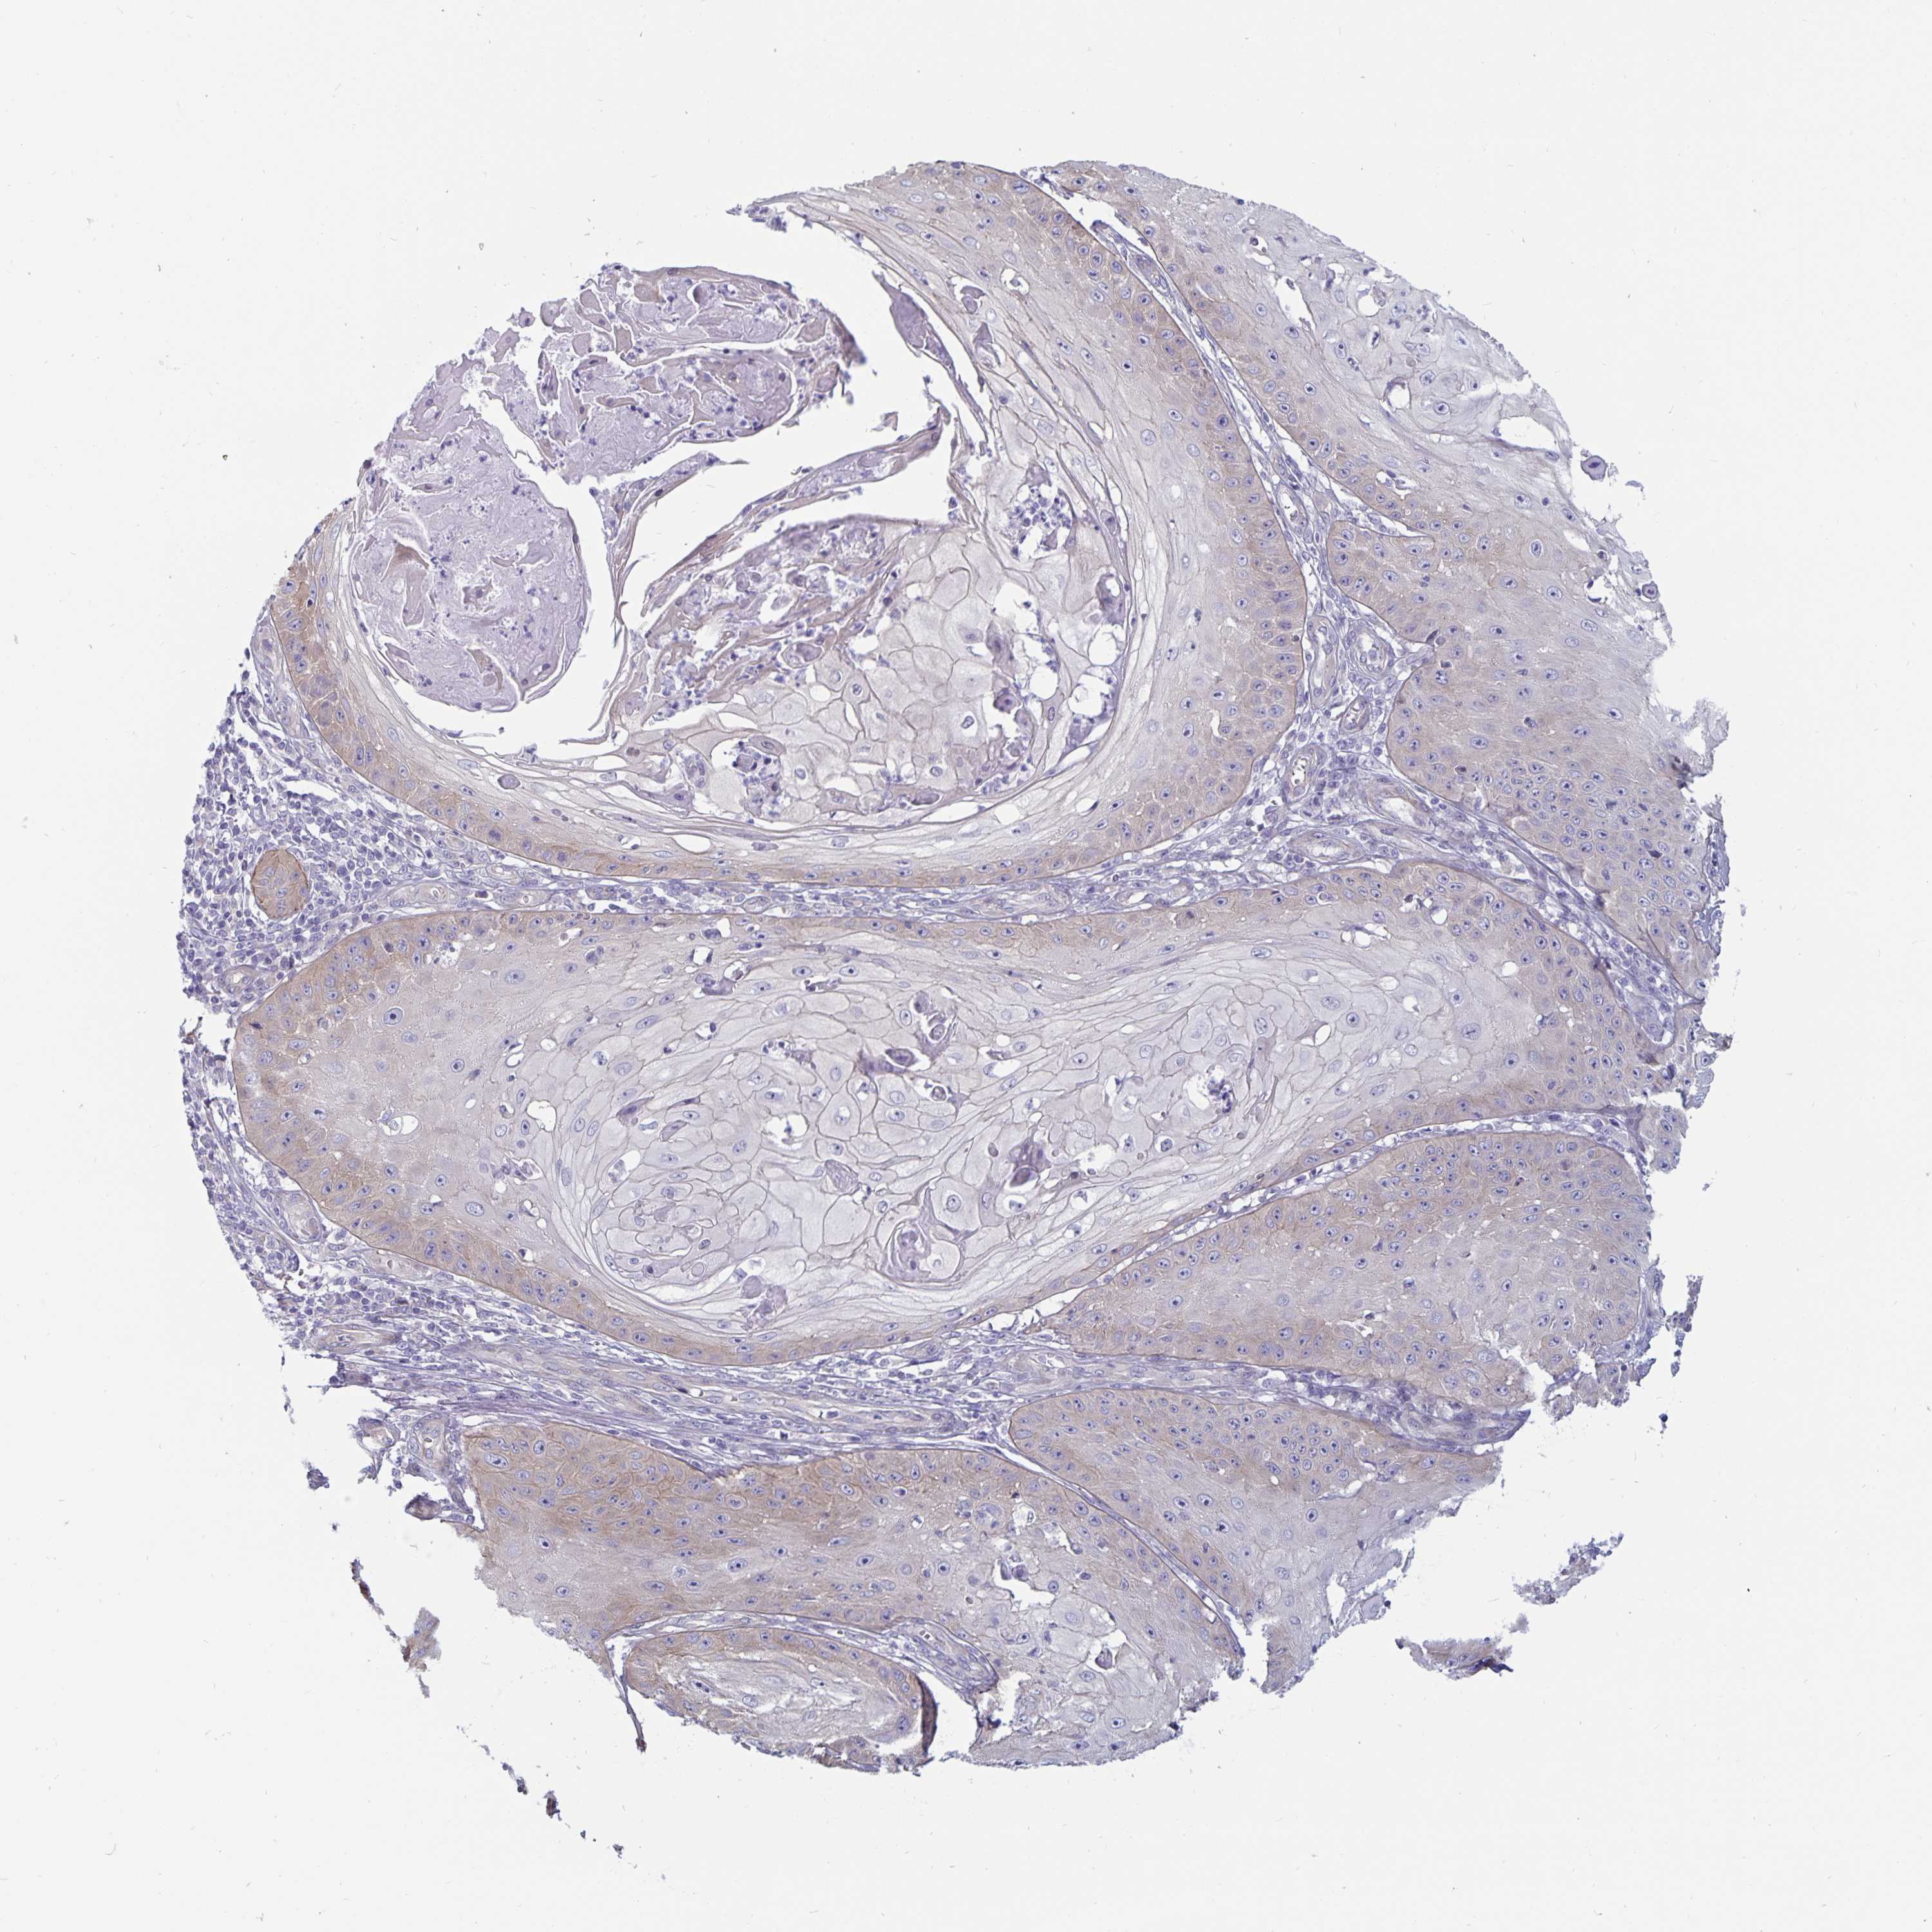

SKIN CANCER - Protein expressioni

A mouse-over function shows sample information and annotation data. Click on an image to view it in a full screen mode. Samples can be filtered based on level of antibody staining by selecting one or several of the following categories: high, medium, low and not detected. The assay and annotation is described here.

Antibody staining in the annotated cell types in the current human tissue is reported as not detected, low, medium, or high, based on conventional immunohistochemistry profiling in selected tissues. This score is based on the combination of the staining intensity and fraction of stained cells.

Each image is clickable and will lead to virtual microscopy that enables deeper exploration of all samples and also displays staining intensity scores, fraction scores and subcellular localization as well as patient and tissue information for each sample.

Antibody HPA039279

Staining

High

Medium

Low

Not detected

Basal cell carcinoma